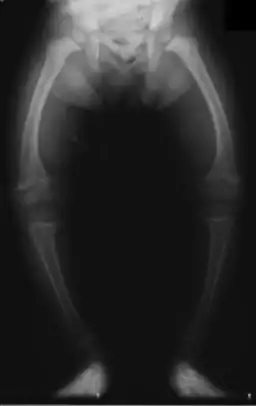

| Significant bilateral nephrocalcinosis (calcification of the kidneys) on a frontal X-ray (radiopacities (white) in the right upper and left upper quadrant of the image), as seen in distal renal tubular acidosis | |

- Nephrocalcinosis (deposition of calcium in the substance of the kidney)

- Bone demineralisation (causing rickets in children and osteomalacia in adults

- Growth deficiency